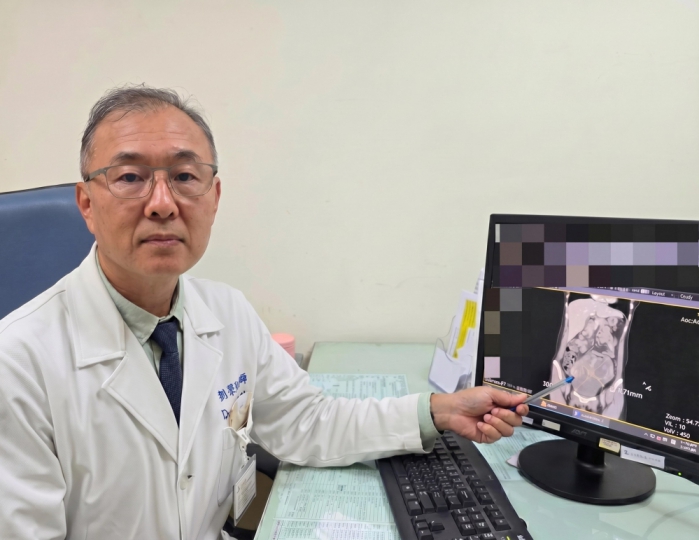

(特派員劉鳳瑩、陳明/苗栗報導)一名44歲未婚女性,持續兩週感到腹痛、腹脹且食慾不振,原以為是腸胃不適,就醫檢查後竟在腹部發現直徑高達 16公分的巨大腫瘤,且癌症指數(CA-125)飆升至 900 U/ml(正常值為 <35 U/ml)。大千綜合醫院婦產科劉榮啟醫師緊急安排手術切除子宮及兩側卵巢,術後病理報告證實為罕見的「同步性子宮內膜癌與卵巢癌(SEOC)」。在醫療團隊悉心治療下,病人至今已成功抗癌滿5年,復原狀況良好。

劉榮啟醫師指出,該個案經病理檢查確認,其子宮與卵巢兩處均為「子宮內膜樣細胞癌」。這種情況在醫學上稱為「同步性子宮內膜癌和卵巢癌(SEOC)」,是一種相當獨特的疾病表現,並非單一癌症轉移至另一器官,而是兩個部位同時發生癌症。SEOC約佔子宮內膜癌病例的5%及卵巢癌病例的10%。這類癌症好發於年輕的停經前女性,雖然同時面對兩種癌症聽起來令人擔憂,但幸運的是,SEOC通常能早期發現,且細胞分化相對較好,預後往往比晚期單一癌症更佳。

該名病人的診斷結果均屬早期(分別為 1c 期與 1a 期)。在接受完整的手術切除後,為了確保徹底清除癌細胞,病人配合進行了6次化學治療,並接受了第2次腹腔鏡探查手術追蹤。至今五年過去,病人定期回診檢查各項指標均正常,已正式跨越癌症醫學上重要的「五年存活期」門檻。

劉榮啟醫師提醒,婦科癌症初期徵兆往往不明顯,如出現持續性的腹脹、腹痛、食慾不振或異常陰道出血,女性朋友應提高警覺,切勿僅當成消化不良或經期失調。早期診斷、早期治療是提高存活率的不二法門,透過超音波檢查與癌症指數篩檢,多數婦科腫瘤都能被及時發現。他鼓勵女性應定期接受婦科檢查,即使面對癌症,現代醫學技術也能提供良好的預後與生活品質。